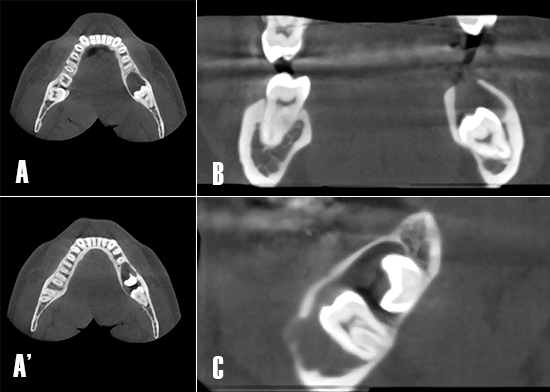

La TCHC (Planmeca ProMax 3D Classic) mostró una extensa imagen osteolítica poco radiodensa en el tercer cuadrante. La lesión era visible en los planos axial, coronal y sagital. Se observó la afectación de la cortical vestibular relacionada a la lesión osteolítica (Fig. 3).

Figura 3. Tomografía computarizada de haz cónico. A) Corte axial. Nótese como la extensión de la lesión osteolítica se extiende en sentido antero posterior afectando la raíz distal de 3.6. A´) Corte axial. En un corte más apical se visualiza la parcialmente la corona de 3.7, y una mayor extensión de la lesión en sentido antero-posterior hasta distal de 3.5. B). Corte coronal. Se observa cómo la lesión osteolítica ha comprometido la integridad de la cortical en sentido craneal. C) Corte axial. La zona poco radiodensa está relacionada a los dientes 3.7 y 3.8 no erupcionados.